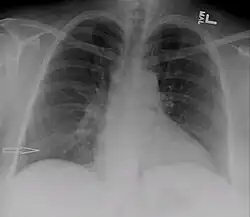

Radiografia de tórax mostrando o urinotórax desaparecendo após o tratamento

O tratamento consiste principalmente em tratar o distúrbio subjacente do trato geniturinário.[6] Requer uma equipe multidisciplinar que inclui um pneumologista e urologista. Um tubo de nefrostomia ou cateter de Foley podem ser usados para aliviar qualquer obstrução subjacente. Quaisquer ferimentos são reparados.[11] Quando o distúrbio subjacente é tratado, o urinotórax se resolve rapidamente. Cirurgia torácica geralmente não é necessária,[3] especialmente se os sintomas respiratórios forem mínimos ou inexistentes.[6] Pleurodese também é ineficaz.[11]

O urinotórax geralmente desaparece espontaneamente, sem recorrência, após o tratamento do distúrbio do trato urinário subjacente.[11]